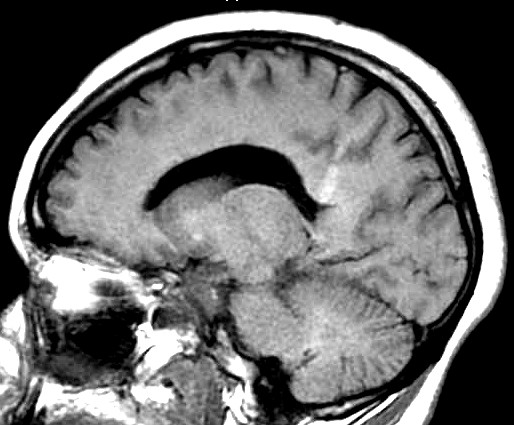

| Fem. 17a. |

| Nódulo sólido homogêneo preenchendo o III ventrículo, com limites precisos, com hipossinal em T1 e hipersinal em T2 e FLAIR, que se impregna por contraste paramagnético. Lesão menor implantada no assoalho do IV ventrículo provavelmente representa disseminação por via liquórica. |

| SAGITAIS, T1 SEM CONTRASTE | T1 COM CONTRASTE | |

| F. 17a. Tumor teratóide rabdóide atípico de III ventrículo. RM | HE | VIM, GFAP | HHF35, desmina, 1A4 | AE1AE3, EMA |